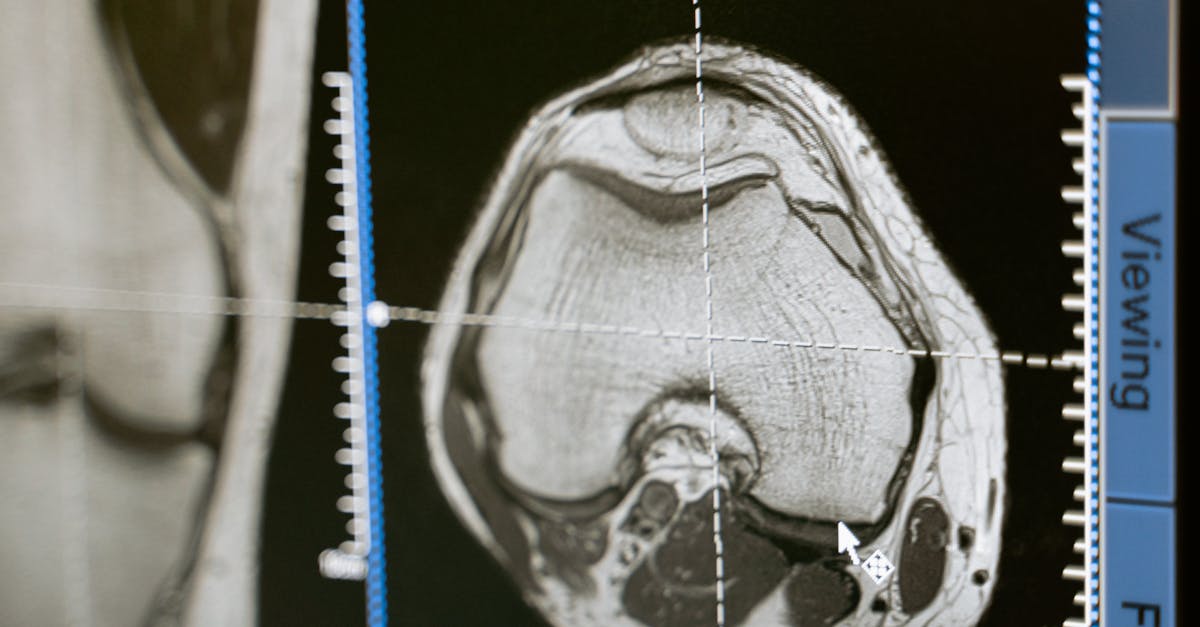

The cost of maintaining radiology facilities is a significant factor contributing to the high pay in this field. Radiology facilities require state-of-the-art equipment and technology to ensure accurate diagnoses and effective treatment planning. These facilities must invest in expensive machinery such as MRI scanners, X-ray machines, and CT scanners, along with the latest software for image processing and data analysis. Moreover, the maintenance and upgrades of these machines demand skilled technicians and engineers, adding to the overall operational costs of the facility.